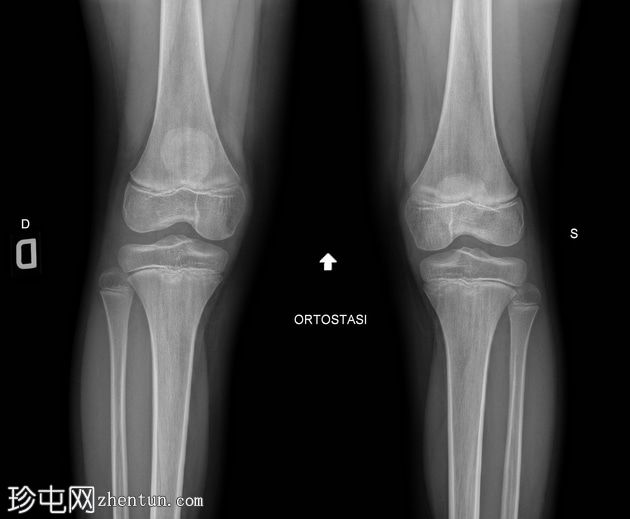

正位 -

负重位

髌骨下极可见一小块薄骨碎片,伴有髌骨高位,Insall-Salvati比值为1.5(V.N. 0.8 - 1.2)。膝前可见软组织肿胀。左膝正常。